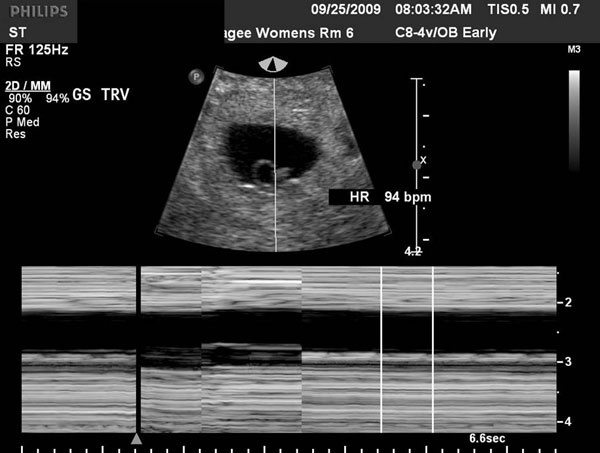

Seeing your baby's heartbeat on an early pregnancy ultrasound is one of the surest indicators that a pregnancy is proceeding as it should. The sections of this tube will go on to form all the structures of the future heart. At 10 weeks pregnant many women are starting to look a little bit pregnant. In general, the risk of miscarriage is much lower once the pregnancy has reached this point and a fetal heartbeat has been detected.

At 8 weeks, cardiac activity seen. Normal fetal heartbeats are 175 beats/min at 8 weeks, 140 beats/min at 20 weeks, and 130 beats/min at. However, it drops slightly in the last 10 weeks. It is becoming firmer and the “pudgy look” is going away.

A slow heart rate may quicken on its own. All blood test n urine test results read excellent at 8 weeks. The normal fetal heart rate is between 115 and 160 bpm. The blood that flows through the fetus is actually more complicated than after the baby is born ( normal heart ). FirstTrimester Ultrasound Early Pregnancy Failure FirstTrimester.

Your baby's heart may beat at a rate of fewer than 110 beats per minute. Predictive value of early embryonic cardiac activity for pregnancy outcome. During the last trimester, the fetal heart rate continues to average 110 to 160 bpm. The normal fetal heart rate is between 115 and 160 bpm. Sonographic detection of fetal abnormalities before 11 weeks of.

A Normal Fetal Heart Will Beat At 110 To 160 Bpm.

The current guidelines of the society of radiologists in ultrasound (sru) establish a crl cutoff of 7 mm, above which one should definitively visualize fetal cardiac activity. This review illustrates the imaging techniques and imaging appearance of various fetal cardiac anomalies seen with various sono graphictechniques. However, newer technology including endovaginal transducers can obtain images of the heart as early as 12 weeks. By the time the embryo measures 2 mm, the fetal heart rate activity should be seen and normal embryos start at under 85 beats per minute heart rate.

Last 10 weeks of pregnancy: At 13 weeks, doctors suggested some more blood related tests and those results also found good. To evaluate the significance of cardiac activity on endovaginal ultrasound in embryos up to 10 mm in size. A fetal heartbeat can be seen and heard during prenatal ultrasound by the sixth week of gestation.